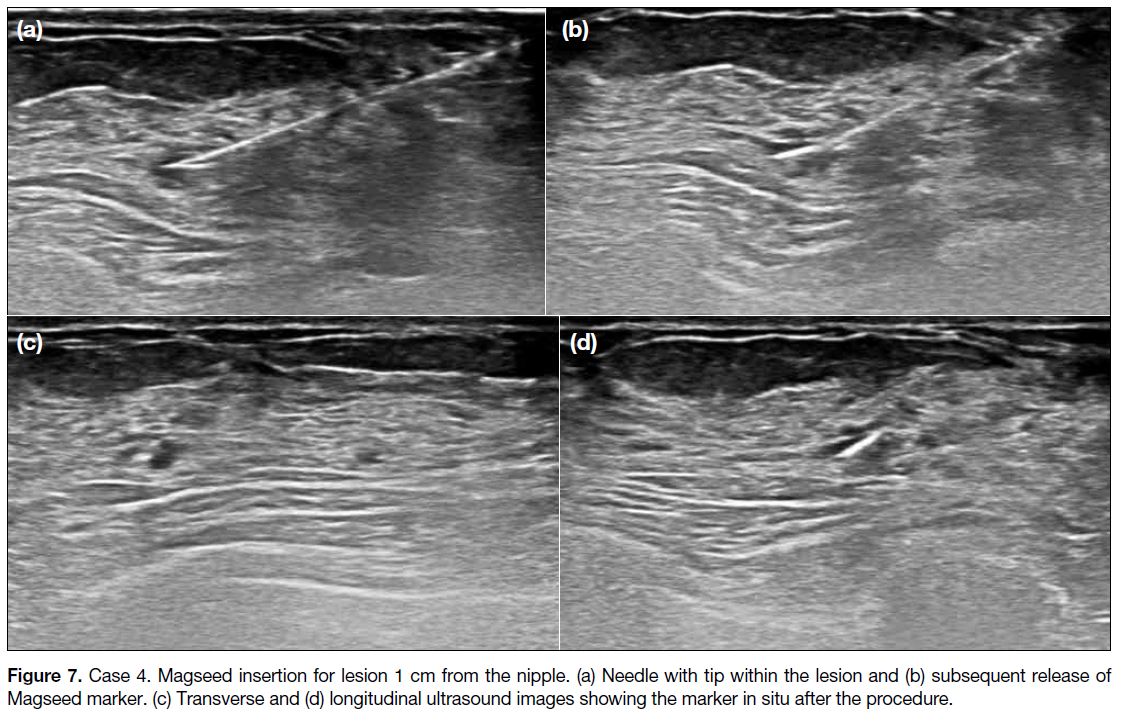

Case 4

A 42-year-old woman with an incidental ultrasound

finding of left breast 12 o’clock position nodule, 1 cm

from the nipple, measuring 6 × 3 × 5 mm, associated

with a prominent duct (Figure 6). Ultrasound-guided

biopsy showed a papillary lesion, likely to be intraductal

papilloma. Magseed insertion was performed before the

procedure and was uneventful (Figure 7). Seventeen days later, lumpectomy was performed and localisation was

uneventful. Pathological examination of the specimen

confirmed intraductal papilloma.

Figure 7. Case 4. Magseed insertion for lesion 1 cm from the nipple. (a) Needle with tip within the lesion and (b) subsequent release of

Magseed marker. (c) Transverse and (d) longitudinal ultrasound images showing the marker in situ after the procedure.